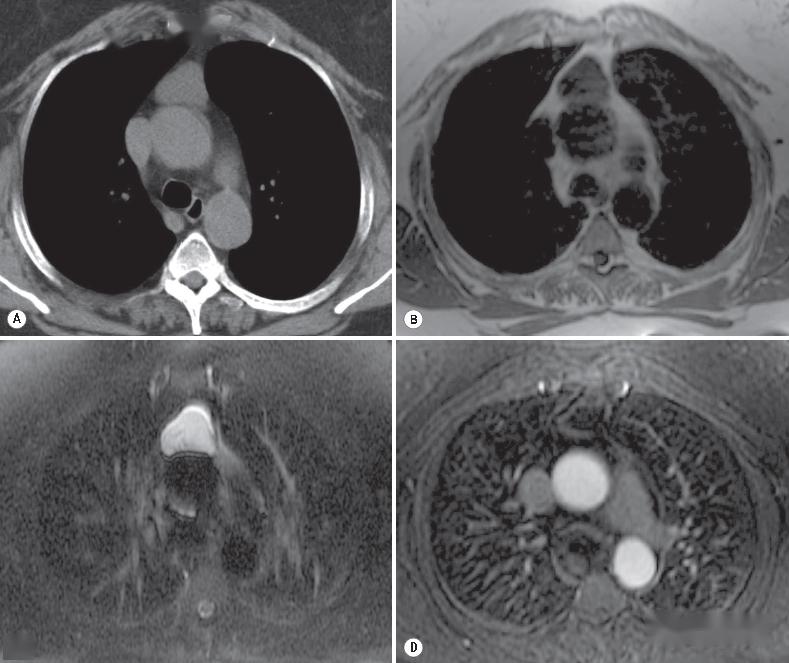

6种纵隔囊性病变的诊断与鉴别